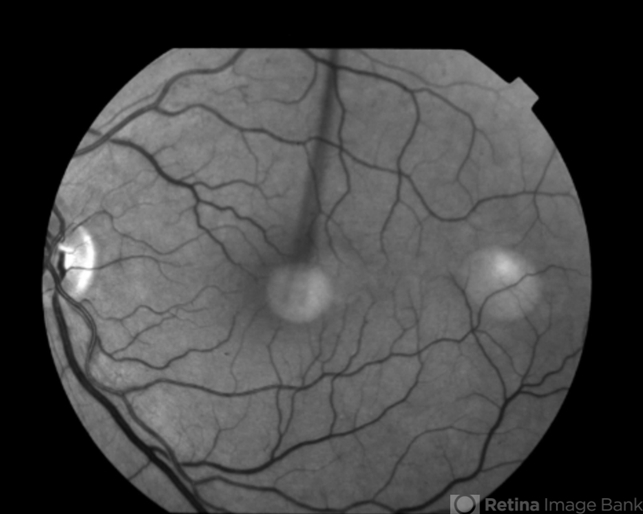

- Multifocal Best Disease

- Condition/keywords

- Best disease, adult vitelliform dystrophy

- Fundus camera

- Macular exam reveals yellow subretinal pigment clumping in each macula, including the foveal area.